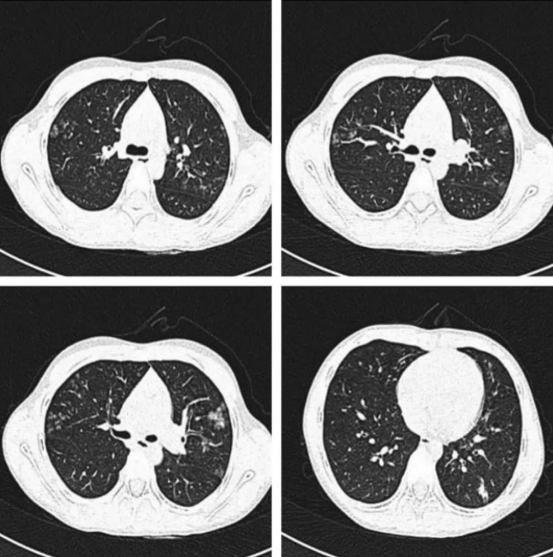

电子烟肺病与传统肺炎CT影像对比图

广州医科大学附属优先医院的呼吸科诊室里,26岁的设计师陈浩第三次被误诊为“过敏性肺炎”。直到支气管肺泡灌洗液检出镍浓度超正常值200倍,才揪出真凶——他每天使用的薄荷味电子烟。

· ‌检测局限‌:常规胸片漏诊率达63%,需高分辨率CT联合金属检测